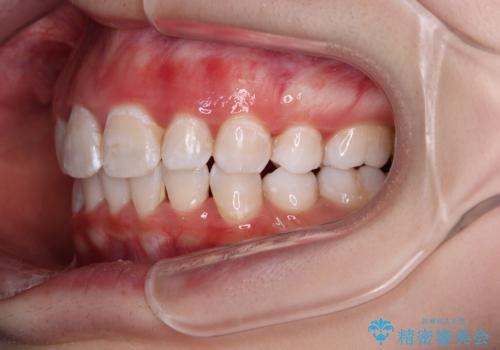

叢生・ディープバイト・突出 ワイヤー装置での抜歯矯正で全てを解決

ディープバイトは、治療を行っていた我々も驚くほど、短期間で劇的に改善することができました。

骨格的に下顎骨が左側にシフトしていたため、上下正中の位置や左側臼歯部の咬合を理想的に仕上げることはできませんでしたが、非常に綺麗な口元を達成することができました。